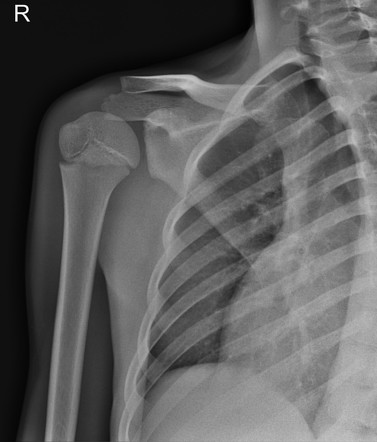

Инструментальная визуализация начинается с рентгенографии, которая проводится с использованием обзорных снимков в двух проекциях — прямой и боковой, а при подозрении на хроническое течение дополняется прицельной рентгеноскопией с контрастным исследованием свищевых каналов. Обзорный режим позволяет определить деструкцию костной ткани, периостальные реакции и наличие секвестров. Контрастное исследование уточняет характер и распространённость воспалительного очага, особенно при наличии осложнений.

Рентгенограмма выявляет следующие анатомические признаки:

- Очаговый остеопороз в диафизарной и метафизарной зоне плечевой кости, проявляющийся как снижение плотности трабекулярного рисунка, часто служит первым признаком воспаления.

- Остеолитические зоны с нечёткими границами, визуализирующиеся как просветления неправильной формы, указывают на прогрессирующее разрушение костной структуры.

- Слоистые периостальные наслоения по типу «луковичной оболочки», определяемые при хроническом процессе, свидетельствуют о многократной стимуляции надкостницы.

- Формирование секвестров, отделённых от окружающей кости, проявляется в виде плотных участков с чёткими границами на фоне остеопороза.

- При контрастной рентгеноскопии возможна визуализация симптома «контрастного хода» — заполнение свищевого канала контрастом, что подтверждает наличие хронической формы остеомиелита.

Рентгенологическое исследование позволяет детально визуализировать следующие диагностические параметры остеомиелита плеча:

- Точные очаги остеолиза, их локализация и распространённость определяются на обзорных снимках, что критически важно для верификации диагноза и планирования лечения.

- Периостальные реакции, фиксируемые при воспалительном процессе, дают представление о его продолжительности и стадии, а также позволяют отличить острые изменения от хронических.

- Формирование секвестров как специфических признаков затяжного течения доступно для надёжной оценки, особенно в сравнении с динамическими снимками.

- Контрастное исследование при наличии свищей визуализирует направления воспалительных трактов и их связь с очагом деструкции, дополняя клиническую картину.

Рентгенографическая визуализация имеет ряд ограничений, и с её помощью не всегда удаётся точно визуализировать следующие аспекты остеомиелита плеча:

- Начальные изменения в костном мозге и сосудистые нарушения не отображаются на снимках, что снижает чувствительность диагностики в остром периоде.

- Мягкотканевые осложнения, такие как параоссальные абсцессы и инфильтраты, не определяются при стандартной рентгенографии и требуют дополнительной оценки.

- Функциональные характеристики воспаления, включая гиперемию и выраженность отёка, остаются вне зоны визуализации, особенно в ранние сроки заболевания.

- Лучевая нагрузка при двупроекционной визуализации плеча составляет от 0,1 до 0,2 мЗв в зависимости от толщины мягких тканей и количества выполненных проекций.